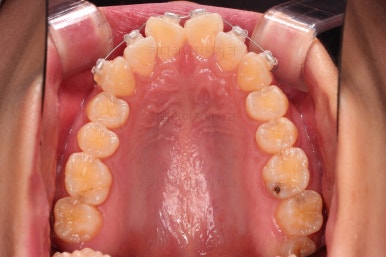

3. 치료경과

우선 윗니 앞니는 장치를 부착했고요.

아래 앞니는 장치 부착 이전에 아래로 앞니를 내려줄 미니스크류를 식립했습니다.

미니스크류가 단단하게 붙었을 시점에 아래 앞니도 장치를 부착하고요.

과개교합 개선을 위해서 미니스크류까지 힘을 줘서 아래 앞니를 내려줍니다.

이번 환자분이 사용한 장치는 엠파워 클리어라고 하는 자가결찰 세라믹 장치입니다.

일반적으로 클리피씨라고 많이 알고 계시는 장치가 "자가결찰 세라믹" 종류이며 여러 종류 중 엠파워 클리어도 있습니다.

제조사만 일본(클리피)이냐 미국(엠파워)이냐의 차이입니다.

아래 앞니는 브라켓보다는 훨씬 작은 미니튜브 장치를 사용했습니다.

과개교합의 경우 브라켓을 부착하게 되면 씹히게 되어 치료과정이 수월하지 못하기 때문이죠.

장치 부착 시점의 장치가 보이는 모습과 입매 변화 관찰해 주시고요.

디테일을 위해서 윗니는 어금니에도 하나씩 장치를 더 부착했고, 아랫니는 바로 뒷 치아에도 장치를 부착했습니다.